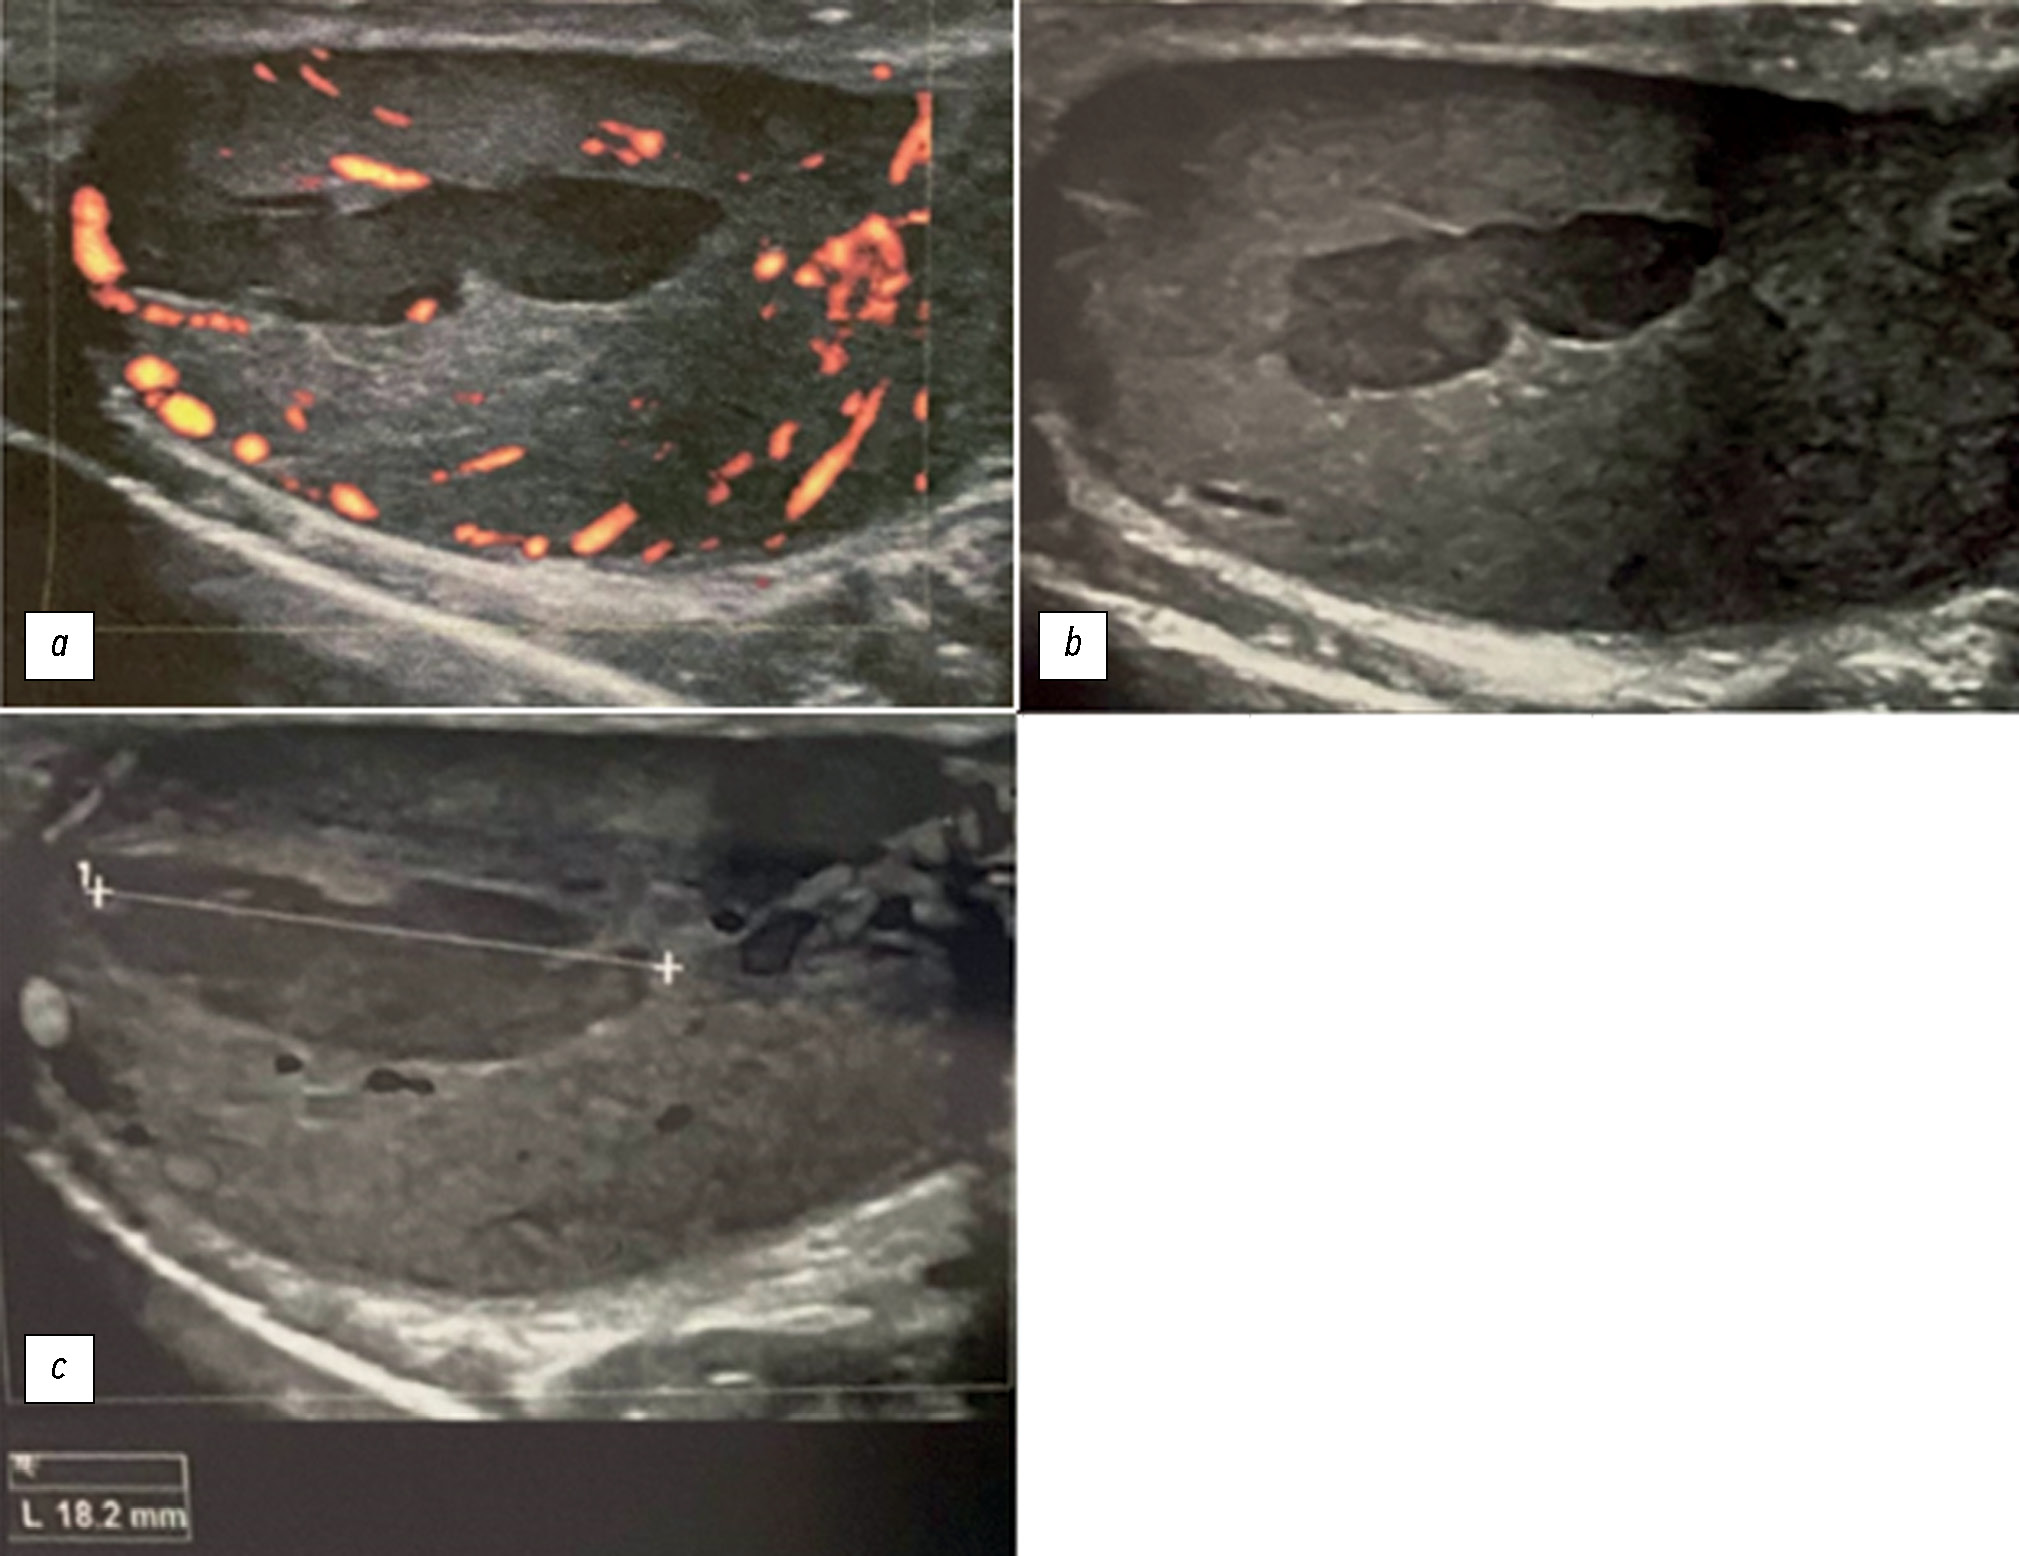

Rare complications of acute epididymitis include ischemia and infarction of the testicles. Both clinically and radiologically, it is challenging to distinguish testicular torsion. In this article we have tried to expand the library of digital images of radiological diagnostic methods used for fast and accurate differential diagnostics. This case emphasizes the significance of a comprehensive radiological assessment and how a multidisciplinary approach is necessary to guarantee an accurate diagnosis. A 24-year-old man experienced severe left testicular pain and came to the hospital 2 weeks later. At the radiology department, he reported that he had for some time painful ejaculations, pain during intercourse (dyspareunia), scrotal redness/swelling, genital inflammation, chills, swollen inguinal lymph nodes, dysuria, and scrotal pain. All diagnostic procedures were performed, first ultrasonography and then magnetic resonance imaging, as required by the urologist. The imaging studies revealed left testicular ischemia, and based on the referred clinical history, a chronic orchid-epididymitis was suspected. Thus, the condition was resolved, not with a left orchidectomy but with medical therapy because the ischemia area was not too large. The patient also had a left varicocele. Images acquired with different magnetic resonance imaging sequences were carefully examined. A rare instance of epididymal orchitis is described as a potentially dangerous complication of epididymitis and must be considered if sudden, severe scrotal pain is experienced to avoid severe consequences. This case can help with optimal patient management and prevent unnecessary interventions.